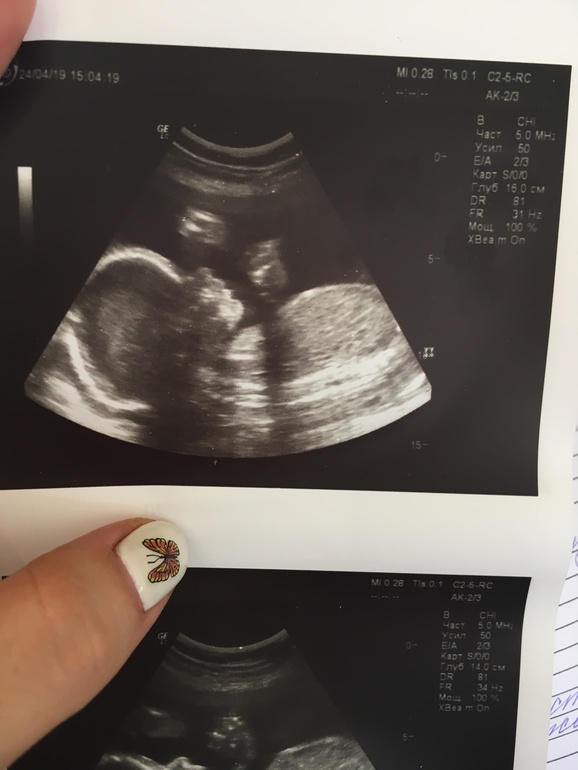

Узи в 25,4 недели

УЗИ, КТГ, доплерВчера (24.04) ходила на узи и вот какое-то двоякое чувство осталось...

Все параметры в норме - посмотрели и мышечный аппарат и внутренние органы - все отлично. Весит мой сынок 770 г (дочка в 25,5 весила 760, а сынок в 24,1 весил 860 - оба родились с весом 3530 и 3550 соответственно на сроке 39,4 и 39 нед), думаю и второй сынок примерно таким же как братик и сестренка родится.

Плацента 0 степени зрелости, толщина 25 мм, воды чистые

А вот, что омрачило - малыш мой развит на полные 24 недели, хотя срок уже 25,4 недели! то есть, почти 1,5 недели отставания. Но узистка успокоила - сказала, что еще догонит. Я, конечно, понимаю что малыши растут скачками, но блин, отставание 1,5 недели все -таки многовато. Буду ждать 31 мая - будет третий скрининг, может порадуют, что догнали срок.

И фото на память: